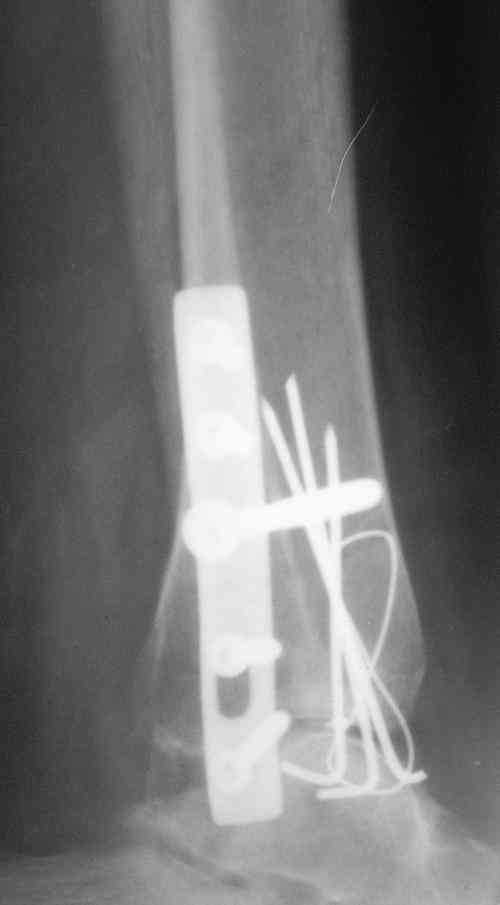

ANDREW 14 Май 2010, 23:44

Завершая презентацию случая хотим показать результат операции. Прооперировали больную в соседнем отделении. На операции выраженый рубцовый процес в области синдесмоза, остеопоротические изменения в области медиальной и латеральной лодыжек. Провели удаление рубцовой ткани, остеосинтез медиальной и латеральной лодыжек с позиционным винтом на синдесмоз. Фото прилагаем. Благодарим за отзывы.